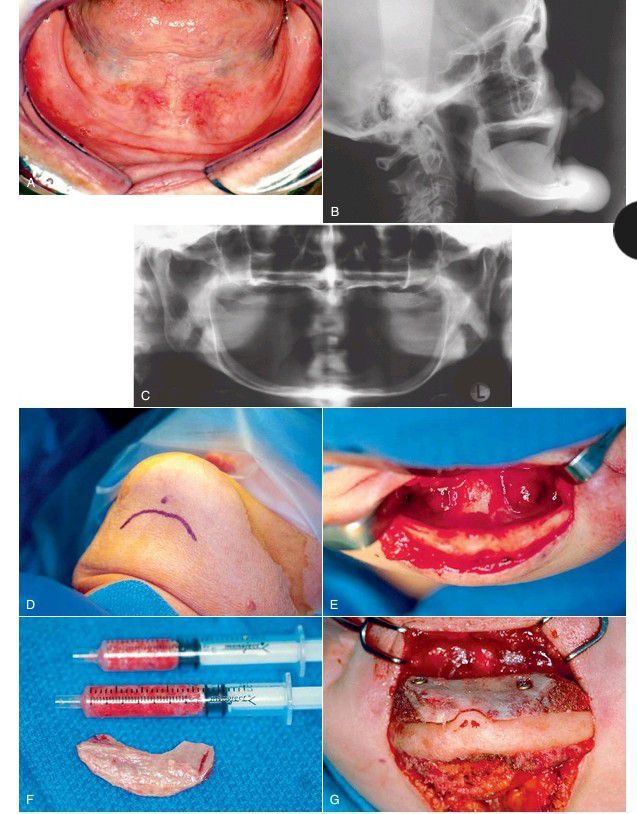

Severely atrophic edentulous mandible treated with anterior iliac crest bone grafting. (A) Initial clinical image of severely atrophic mandible. (B) Lateral cephalometric radiograph. (C) Panorex showing extreme atrophy of entire mandible. (D) Extraoral approach for bone grafting. (E) Exposure of anterior mandible. (F) Autogenous bone harvested from the iliac crest. The graft includes a corticocancellous block as well as additional marrow. (G) Grafts in place.